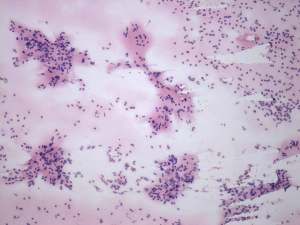

Cytology was performed and resulted in thyroiditis. There were scattered number of lymphocytes and multinucleated giant cells were also found.

The presence of multinucleated giant cells composed of epithelioid cells resembles that observed in de Quervain's thyroiditis. This type of multinucleated cells occurs rarely in autoimmune thyroiditis.